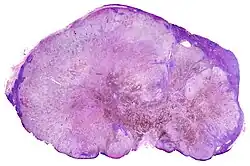

Micrograph of thyroid cancer (papillary thyroid carcinoma) in a lymph node of the neck. H&E stain

Micrograph of thyroid cancer (papillary thyroid carcinoma) in a lymph node of the neck. H&E stain -